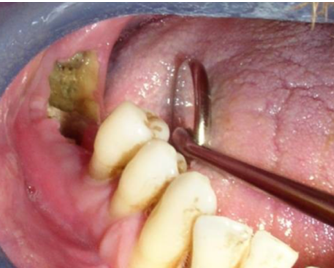

What does this clinical image show?

Medication related Osteonecrosis of the jaw OR osteoradionecrosis.

How do we know if a patient has osteoradionecrosis or MRONJ

You need to look at the patients medical history;

It is only osteoradionecrosis if the patient has had radiotherapy to treat head and neck cancer.

Otherwise it is Medication related osteonecrosis of the jaw. This can be caused by: Bisphosphonates, RANKL inhbitors e.g. Denosumab

and antiangiogenic e.g. Bevacizumab.

(So think patients with osteoporosis or cancer)